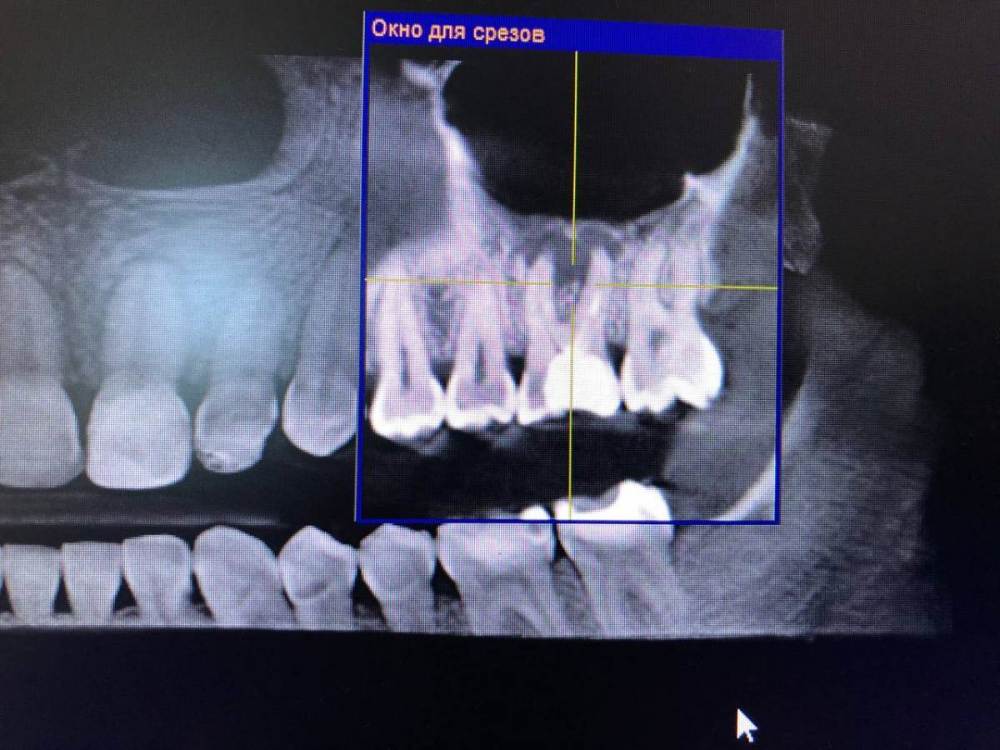

Екатерина Б. Опубликовано 19 августа, 2022 Поделиться Опубликовано 19 августа, 2022 Добрый день! Очень нуждаюсь во мнение специалистов) Сделала снимок КТ, на котором обнаружена киста 6го зуба в верхней левой части челюсти. Сказали, что только под удаление и установку имплантата. Вот хочу понять так ли это? Или всё же есть возможность сохранить свой зуб лечением? Подскажите, пожалуйста, есть ли смысл спасать свой зуб? Или утвердительно-УДАЛЯЕМ? Заранее благодарю за ответы) Ссылка на комментарий

Екатерина Б. Опубликовано 19 августа, 2022 Автор Поделиться Опубликовано 19 августа, 2022 Спасибо за ваш ответ)! Самое интересное, мне дали понять, что данная процедура не дает гарантии, что после нее -через пол года, например, зуб снова не даст о себе знать в плохом смысле. Что область корня зуба сильно поражена кистой. И что костная ткань тоже не в лучшем состоянии. Видимо это как-то заметно на снимке..честно говоря, я не очень в этом разбираюсь)). Именно поэтому, мне хотелось бы еще услышать мнения... Ссылка на комментарий